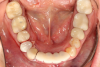

The next case follows the digital protocol for fully guided surgery and prosthetics. A CBCT radiograph, digital impression, and digital photography were the cornerstones to the success of this case. The 3D data set was electronically delivered to the dental laboratory. The data were merged and the process to develop the plan was initiated. The use of CBCT was essential in this case, particularly due to minimal space for placement of individual implants and single-unit crowns. The patient's chief concern was that she wanted to have single-unit crowns instead of fixed crown-and-bridge restorations because she was worried that she would someday find herself in an assisted-living facility; if that were to happen, she wondered, who would help floss under her bridge work? Her decision was to have single implants with individual crowns. CBCT technology is much more accurate in evaluating space maintenance and management.10 Periapicals in the past were rather close for calculating spacing; however, the CBCT identifies the buccal-lingual dimensions as well as the mesial-distal measurements. On review of the completed proposals for implant placement and provisionals, it was determined that there was sufficient spacing for implant placement to allow appropriate emergence profiles for the provisionals and then eventually the final single-unit cemented crowns. The proposal was accepted, and a 3D-printed surgical stent was fabricated, along with the PMMA provisionals (Figure 29 through Figure 35).

Fig 42. Occlusal view of prepared implants.

Figure 42